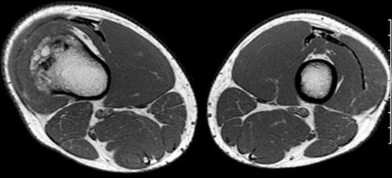

A 15-year-old male presents with deep knee pain awakening him at night. Radiographs show a permeative destructive lesion in the distal femoral metaphysis with a 'sunburst' periosteal reaction and Codman's triangle.

Biopsy confirms high-grade conventional osteosarcoma. What is the most critical prognostic factor for long-term overall survival in this patient?

Explanation

For localized high-grade osteosarcoma, the most important prognostic indicator is the histologic response to neoadjuvant chemotherapy. This is evaluated during the definitive resection. A 'good response' is typically defined as greater than 90% or 99% tumor necrosis. Patients who achieve this level of necrosis have a significantly improved disease-free and overall survival rate compared to 'poor responders' who have extensive viable tumor cells remaining.